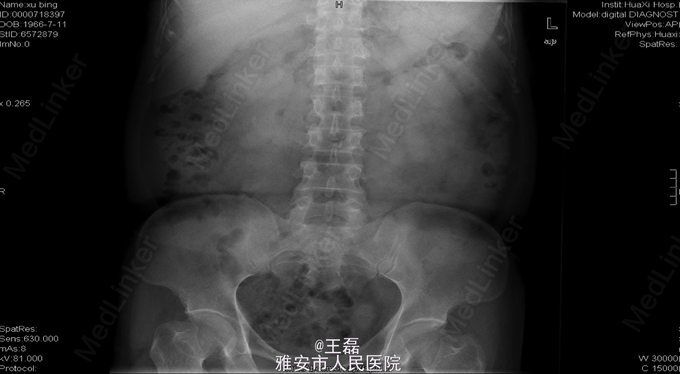

术前KUB:右肾结石:1.0*0.9cm

诊断为右肾下盏结石; 手术:右侧输尿管软镜钬激光碎石取石术